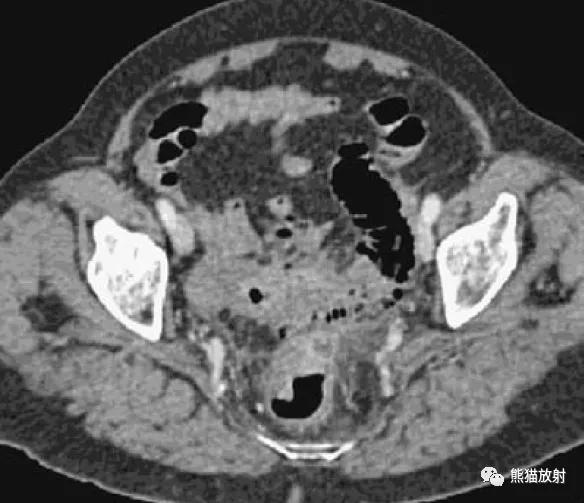

乙状结肠憩室炎。CT(A)和MR(B,C)图像。多发憩室,相应肠壁增厚、周围间隙混浊,不全肠梗阻。